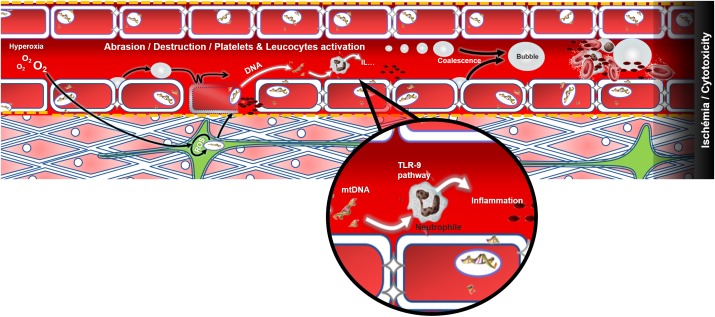

Patients arrive at different times after the dive but overall they present themselves at the onset of the disease (except for the Ctrl+). It is also necessary to take into account the environmental context and the various inter-individual susceptibilities of humans, and therefore consider the possibility of profiles that are particularly sensitive to hyperoxia. The possibility of confounding factors escaping the study context must also be considered. Asthenia, paresthesia or the feeling of chest tightness are as attributable to psychological stress as they are to physical or biochemical stress. So a simple mitochondrial fault inducing hypoxia, and resulting from oxidative stress during the dive, may have equal central, medullary or vestibular repercussions, provided that a localized anatomical fragility is expressed in the patient. In addition, symptoms are not exclusive and overlap. The various components of DCS compete in the realization and maintenance of a multi-factorial ischaemia where the cytotoxic phenomena overlap little by little with the effects of tissue oxygen deficit (Figure 4).

FIGURE 4.

Modeling of decompression sickness incorporating the genesis and increase of bubbles at the vascular level. Excess oxygen could be the source of oxidative stress which alters mitochondrial function and weakens the vascular (red), neuronal (green) or muscular (pink) tissues for example. Following decompression, the bubbles may either abrade the endothelium and leave the collagen bare (yellow dots) which will activate the platelets (in black), or activate the platelets and the immune system directly when they make contact, or even cause an obstruction to the circulation. A dark area is established in the end downstream of the thrombosis: this last illustrating the sum of effects, like cytotoxicity and ischemia among athers, that may spread in the body and contribute to the vicious circle of DCS which is poorly understood. The release of mtDNA would be concomitant and would also participate in the activation of the immune system.